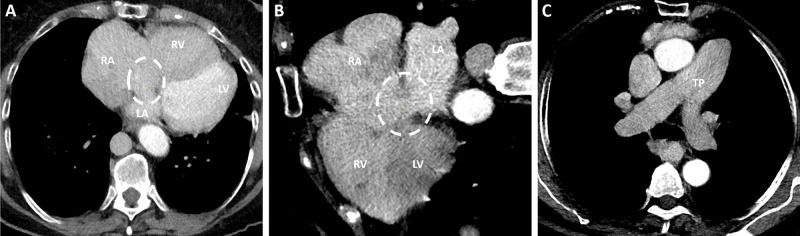

Abstract Image